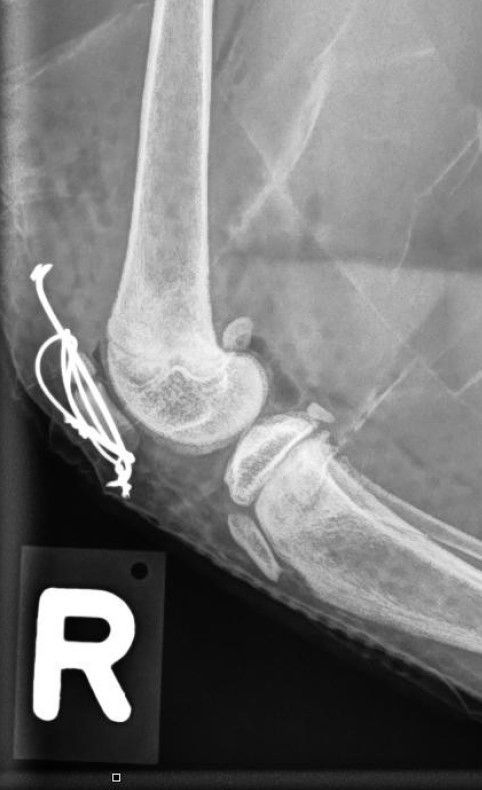

Operation

Wir überweisen den jungen Kater an eine nahegelegen Chirurgiepraxis. Dort wird der Bruch mittels einer sogenannten Zuggurtung versorgt: Diese Methode beinhaltet ein System an Nägeln und Drähten, welche bei Knochenbrüchen eingesetzt werden, die einer Zugkraft ausgesetzt sind.

Weiterer Verlauf

Hardy erholt sich gut von der Operation. Der Aufenthalt in einem grossen Käfig, der während 6-8 Wochen ein allzu wildes Herumturnen verhindern soll, erweist sich aber als Herausforderung. Bei der Kontrolle 4 Tage nach Operation ist auch ersichtlich, dass sich Hardy etwas an der Wunde geleckt hat. Da das Tragen eines Halskragens erwiesenermassen völlig unmöglich ist, geben wir dem Besitzer einen Bitterspray mit, um das Lecken zu verhindern. Geplant ist ein Ziehen der Nähte in einer Woche. Kontrollröntgen sind 6 Wochen nach der Operation vorgesehen.

Ein Bruch der Kniescheibe ist hingegen eine sehr ungewöhnliche Verletzung bei Hunden und Katzen; es wird geschätzt, dass sie nur 0.25% aller Knochenbrüche ausmachen. Da durch die Fraktur das Kniegelenk nicht mehr korrekt bewegt werden kann, wird der Bruch chirurgisch versorgt. Das Problem: Auf den Frakturspalt wirken v.A. Zugkräfte ein, welche die Bruchstücke auseinanderziehen und so eine Heilung erschweren. Im Gegensatz dazu wirken z.B. beim Bruch des Unterschenkelknochenschafts auf den Bruchspalt hauptsächlich Druckkräfte ein, welche den Frakturspalt komprimieren und so eine Heilung einfacher machen. Bei einer Kniescheibe wird deshalb mit der sogenannten Zuggurtung ein System aus Nägeln und Drähten verwendet, um diese Zugkräfte zu neutralisieren.

Da bei einer so jungen Katze der Knochenumsatz sehr hoch ist, besteht die Hoffnung, dass der Bruch komplikationslos abheilen wird.